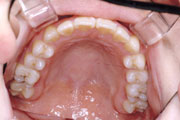

一般矯正の症例

症例1:乱杭歯(叢生)